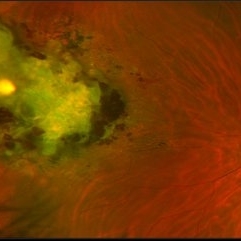

Ocular Parasitosis

Color fundus montage of an 12-year-old boy with ocular parasitosis affecting his left eye. Patient presented with decreased vision and recent travel to Florida. The specimen was lost in the lab and was never recovered.

Photographer: Olivia Rainey

Imaging device: Topcon 50dx

Condition/keywords: color fundus photograph, color photo, intraocular foreign body, left eye, montage, parasite